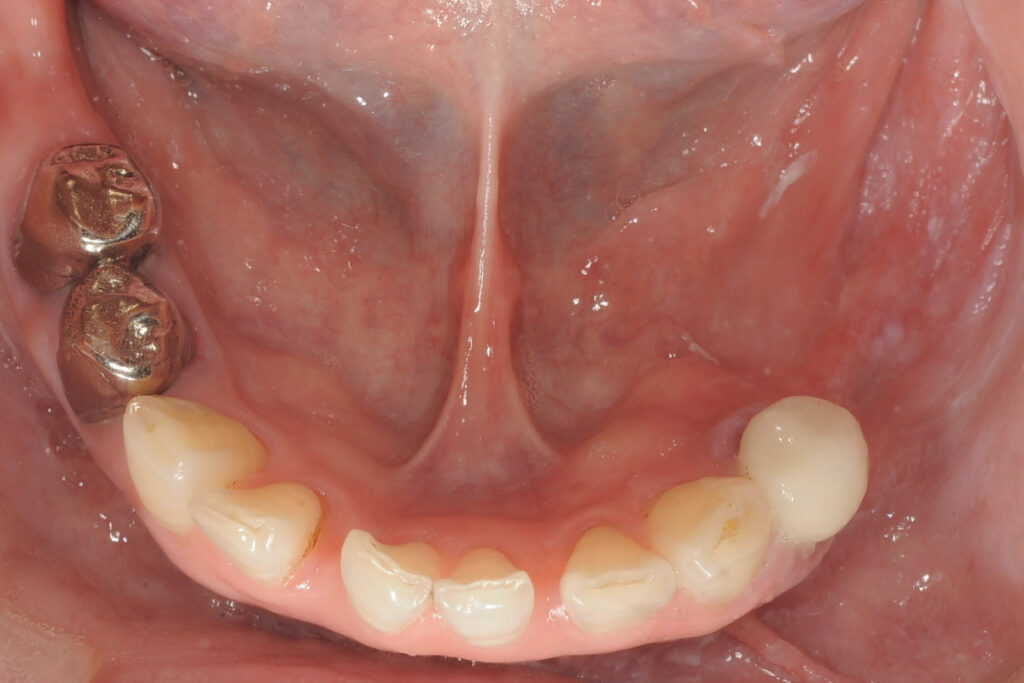

症例1|骨量不足で断られたケース

――「骨が足りない」というNOを、どう再定義したか

■背景

50代女性。下顎奥歯の欠損。片側咀嚼が続き、噛み合わせ全体への不安が強まっていました。他院でインプラント相談を行いましたが、「骨量が足りないため難しい」と説明され、治療を断念しました。

この時点で患者が抱えるのは、治療の可否だけではありません。「放置して悪化するのではないか」「しかし怖いものに踏み込むのも不安」という、迷いも生まれます。

■問題点の整理

- 骨量が少ないこと自体は事実

- ただし、本来検討すべきは

- 骨造成を行えば成立する可能性があるのか

- 成立させた場合に長期安定が見込める条件か

- つまり「骨が少ない」という確認だけで終わり、成立条件の判定がなされていなかった

■当院での判断

吉留英俊が行ったのは、「できるかどうか」ではなく、「成立させた場合に安定するかどうか」の検討です。

- 骨造成(GBR)を併用した場合の骨の獲得量の見込み

- 咬合負荷の方向(どの方向に力がかかるか)と分散の設計

- 術後管理を継続できる条件(通院、清掃、生活習慣)

これらを精査した結果、条件付きでできると判断しました。

- 条件を満たせない場合 → 実施しない

- 条件を満たせる場合のみ → 治療を選択肢として提示

「できます」と言って押すのではありません。成立条件と限界を先に共有し、患者が納得して選べる状態を作ってから実施します。

■選択した治療

- 骨造成(GBR)を併用したインプラント治療

- 治療期間・リスク・限界を事前に共有したうえで実施

■結果としての状態

治療は完遂しました。現在は定期管理下で、機能的・構造的に安定した状態を維持しています。患者の実感は「噛める」だけではありません。「これ以上悪化させないで済む」という安心が残りました。